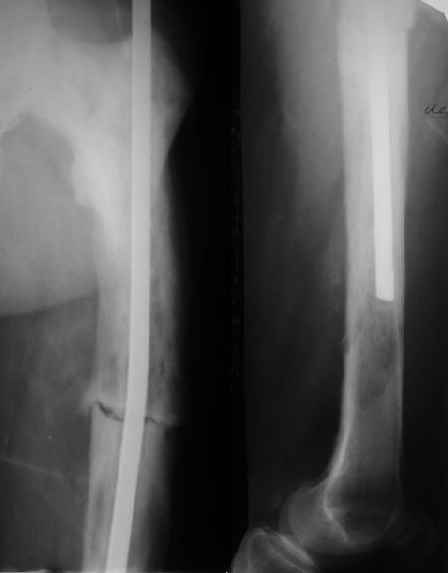

Пациент 82 лет, поступил через 5 мес. с несросшимся переломом после открытого интрамедуллярного остеосинтеза. Выполнили реостеосинтез стержнем 12 мм. ( мах. доступного нам в 2003 г.) Через 4 мес динамизация. В течении 2х лет сращения нет, тем не менее конечность опорна (ходит с тростью). От очередного реостеосинтеза отказались из-за сопутств. патологии.